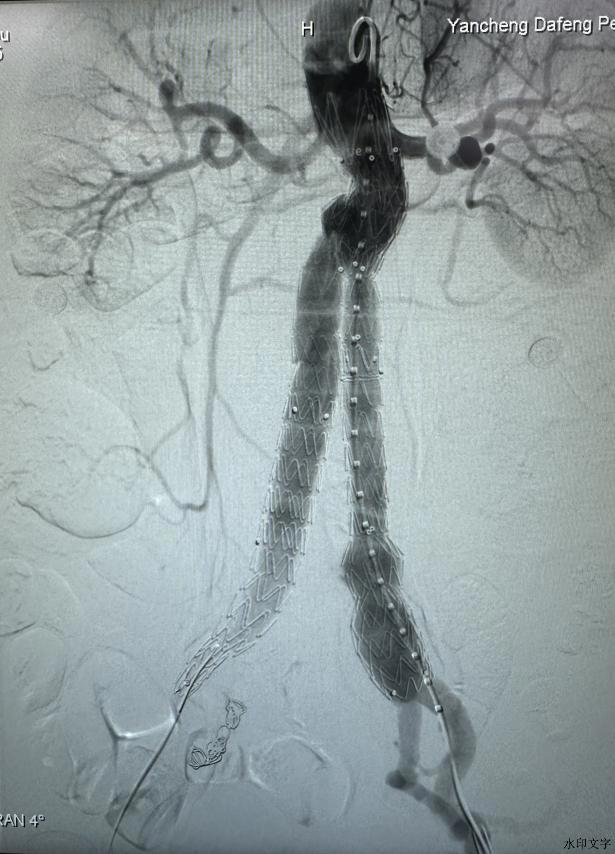

为确保手术万无一失,我院血管外科丁勇主任迅速组织院内外专家召开多学科会诊(MDT),结合患者病史和最新影像学检查结果,制定了详尽的手术方案。在充分评估患者风险的基础上,团队决定采用腹主动脉瘤腔内修复术(EVAR),这一技术以微创性、高精准度以及术后恢复快的优势成为治疗腹主动脉瘤的首选方法。手术当天,血管外科团队在介入导管室中展开这场生命保卫战,在省专家指导下和麻醉科、介入科等多学科团队的通力协作下,历时3小时顺利完成导丝定位、腔内个性化定制支架精准置放,恢复了腹主动脉的正常血流功能。手术结束后,患者被转入ICU进行监护,ICU团队密切监测患者的生命体征,确保患者在术后能够平稳度过危险期,转回血管外科普通病房,经过医护团队全面而精细的术后管理,患者病情恢复良好。

术中造影所示腹主动脉瘤

术中支架置入后